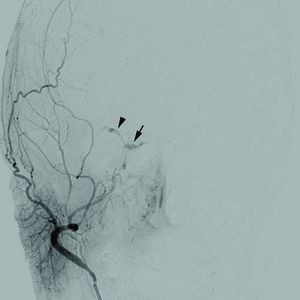

| مرض وعائي دماغي Cerebrovascular disease | |

| Cerebral angiogram of a carotid-cavernous fistula | |